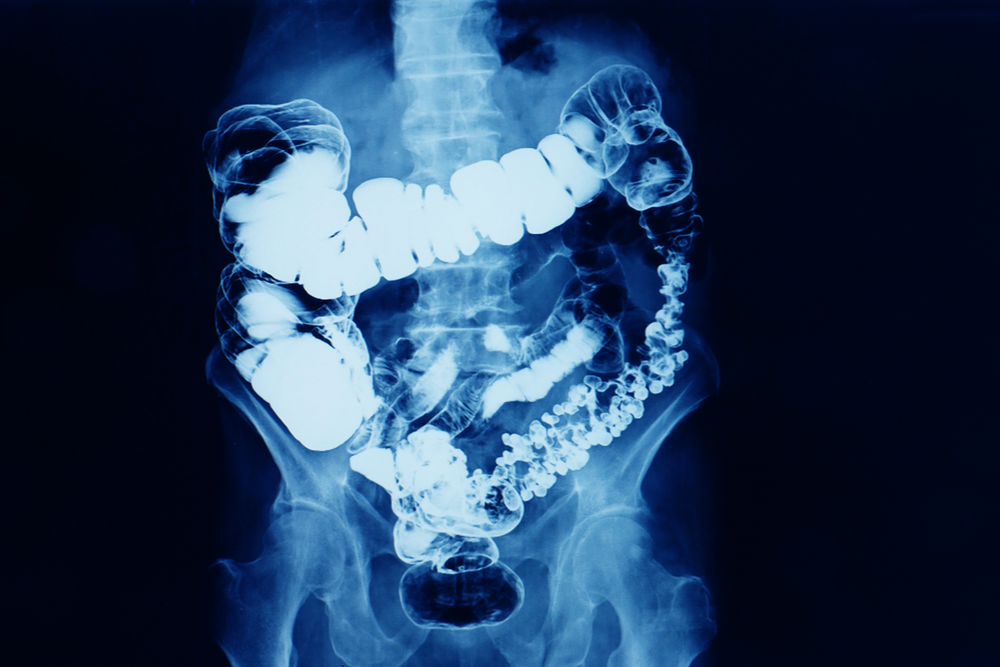

Онкологические заболевания нередко возникают из-за несбалансированной диеты, в которой слишком много переработанного мяса и сахара, а круп, фруктов, овощей и молочных продуктов недостаточно. Мы разобрались, что нужно есть, чтобы не было рака кишечника.